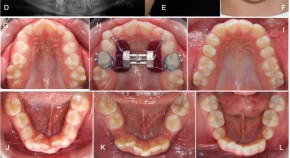

Bringing together a selection of articles from across the BDJ Portfolio, this Collection relates to the theory and practice of orthodontics. It features the BDJ Special Issue on the Orthodontic-Restorative Interface with contributions by leading national and international clinicians and researchers. Guest edited by Padhraig Fleming, it provides a contemporary, international perspective on adult orthodontics and combined orthodontic-restorative care.